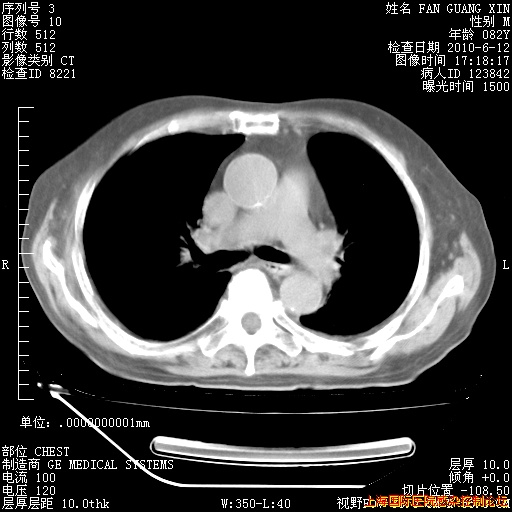

补发6月12日肺部CT肺窗

6月12日肺窗